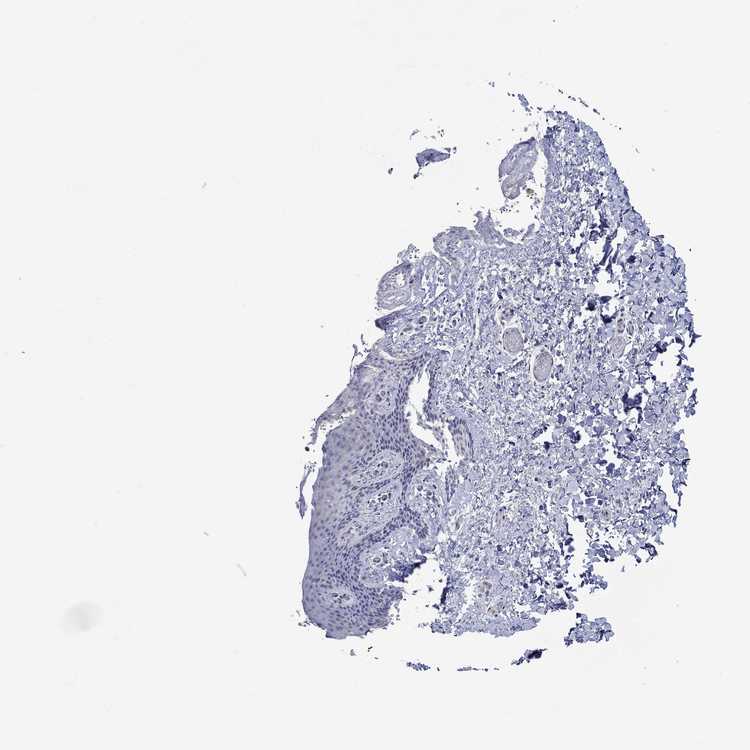

SKIN 1 - Antibody stainingi

Antibody staining in the annotated cell types in the current human tissue is reported as not detected, low, medium, or high, based on conventional immunohistochemistry profiling in selected tissues. This score is based on the combination of the staining intensity and fraction of stained cells.

Each image is clickable and will lead to virtual microscopy that enables deeper exploration of all samples and also displays staining intensity scores, fraction scores and subcellular localization as well as patient and tissue information for each sample.

Antibody HPA044354Antibody HPA073565

Langerhans Not detectedNot detected

Fibroblasts Not detectedNot detected

Keratinocytes LowNot detected

Melanocytes Not detectedNot detected